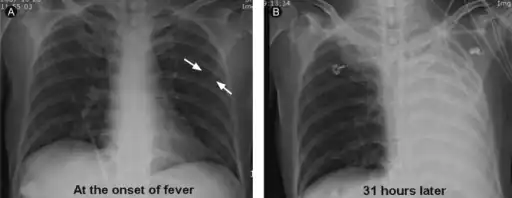

It is a common misconception and pure speculation that atelectasis causes fever. A study of 100 post-op patients followed with serial chest X-rays and temperature measurements showed that the incidence of fever decreased as the incidence of atelectasis increased.[4] A recent review article summarizing the available published evidence on the association between atelectasis and post-op fever concluded that there is no clinical evidence supporting this speculation.[5]

Clinically significant atelectasis is generally visible on chest X-ray; findings can include lung opacification and/or loss of lung volume. Post-surgical atelectasis will be bibasal in pattern. Chest CT or bronchoscopy may be necessary if the cause of atelectasis is not clinically apparent. Direct signs of atelectasis include displacement of interlobar fissures and mobile structures within the thorax, overinflation of the unaffected ipsilateral lobe or contralateral lung, and opacification of the collapsed lobe. In addition to clinically significant findings on chest X-rays, patients may present with indirect signs and symptoms such as elevation of the diaphragm, shifting of the trachea, heart and mediastinum; displacement of the hilus and shifting granulomas.[10]

- a) Subsegmental atelectasis b) atelectasis had rapidly progressed the following day